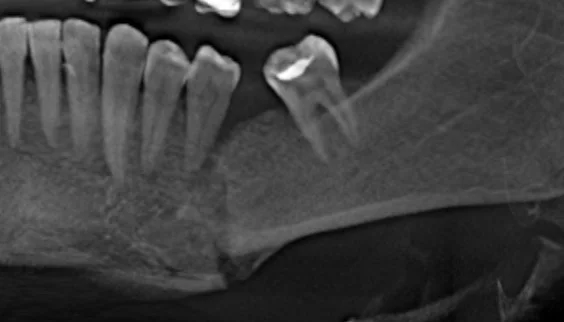

Давайте сравним снимки зубов, сделанные при помощи визиографа (слева), и при помощи компьютерной томографии (справа).

Как говорится, ощутите разницу. КТ - гораздо более точная и своевременная диагностика.

Воссоздавая орган (зуб) или даже совокупность органов, необходимо предельно точно знать исходную ситуацию. Корни зубов, каналы зубов, крупные сосудисто-нервные пучки, идущие внутри костной ткани, верхнечелюстная пазуха во всех подробностях и т.д. - в неискаженном виде все это можно увидеть только на компьютерной томограмме. Стоит ли говорить, что все эти структуры важны для имплантации, так как могут быть легко поврежденфы в ходе операции.

| Оценка степени тяжести при заболеваниях десен (пародонтита). | Определение положения ретинированных и дистопированных зубов | Диагностика различных заболеваний височно-нижнечелюстных суставов. | Диагностика и оценка переломов корней зубов |